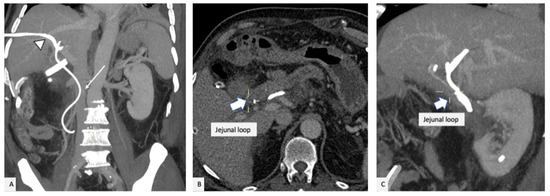

2. Case Presentation